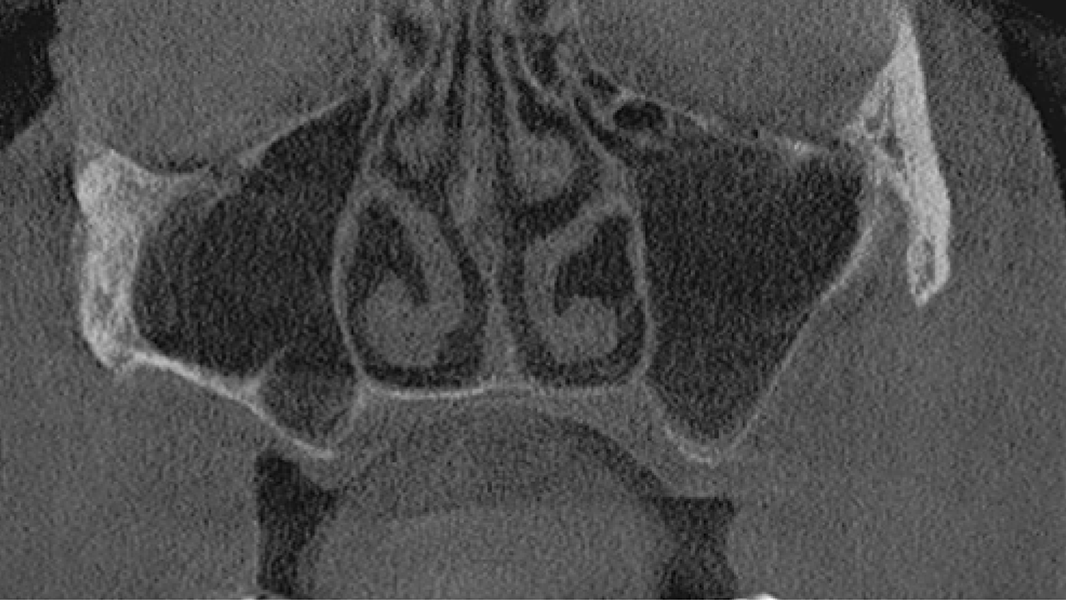

3 Kloss et al. Clin Case Rep. 2020, 8(5):886-893.

5 Kloss et al. Clin Oral Implants Res. 2018, 29, 1163.